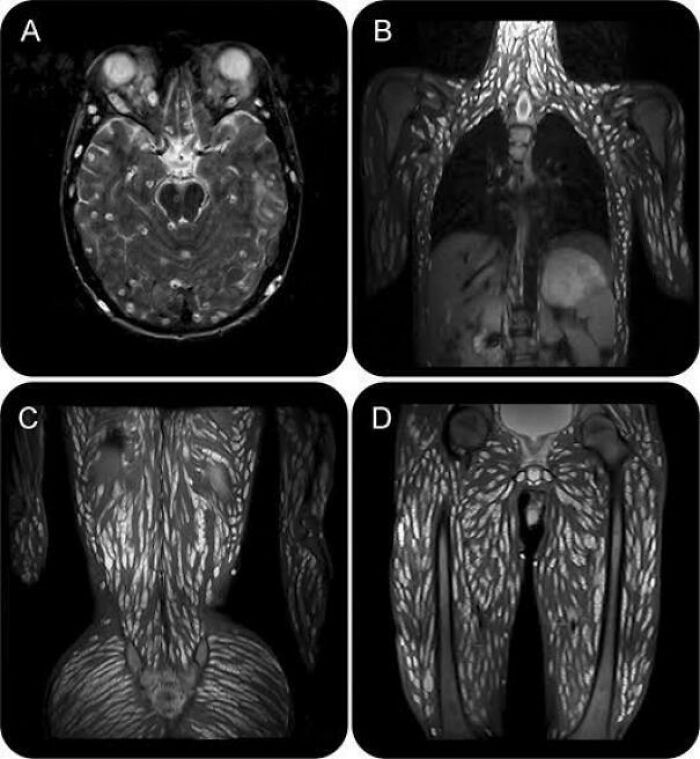

Person Infected With Worm Parasites From Eating Raw Pork 🤢